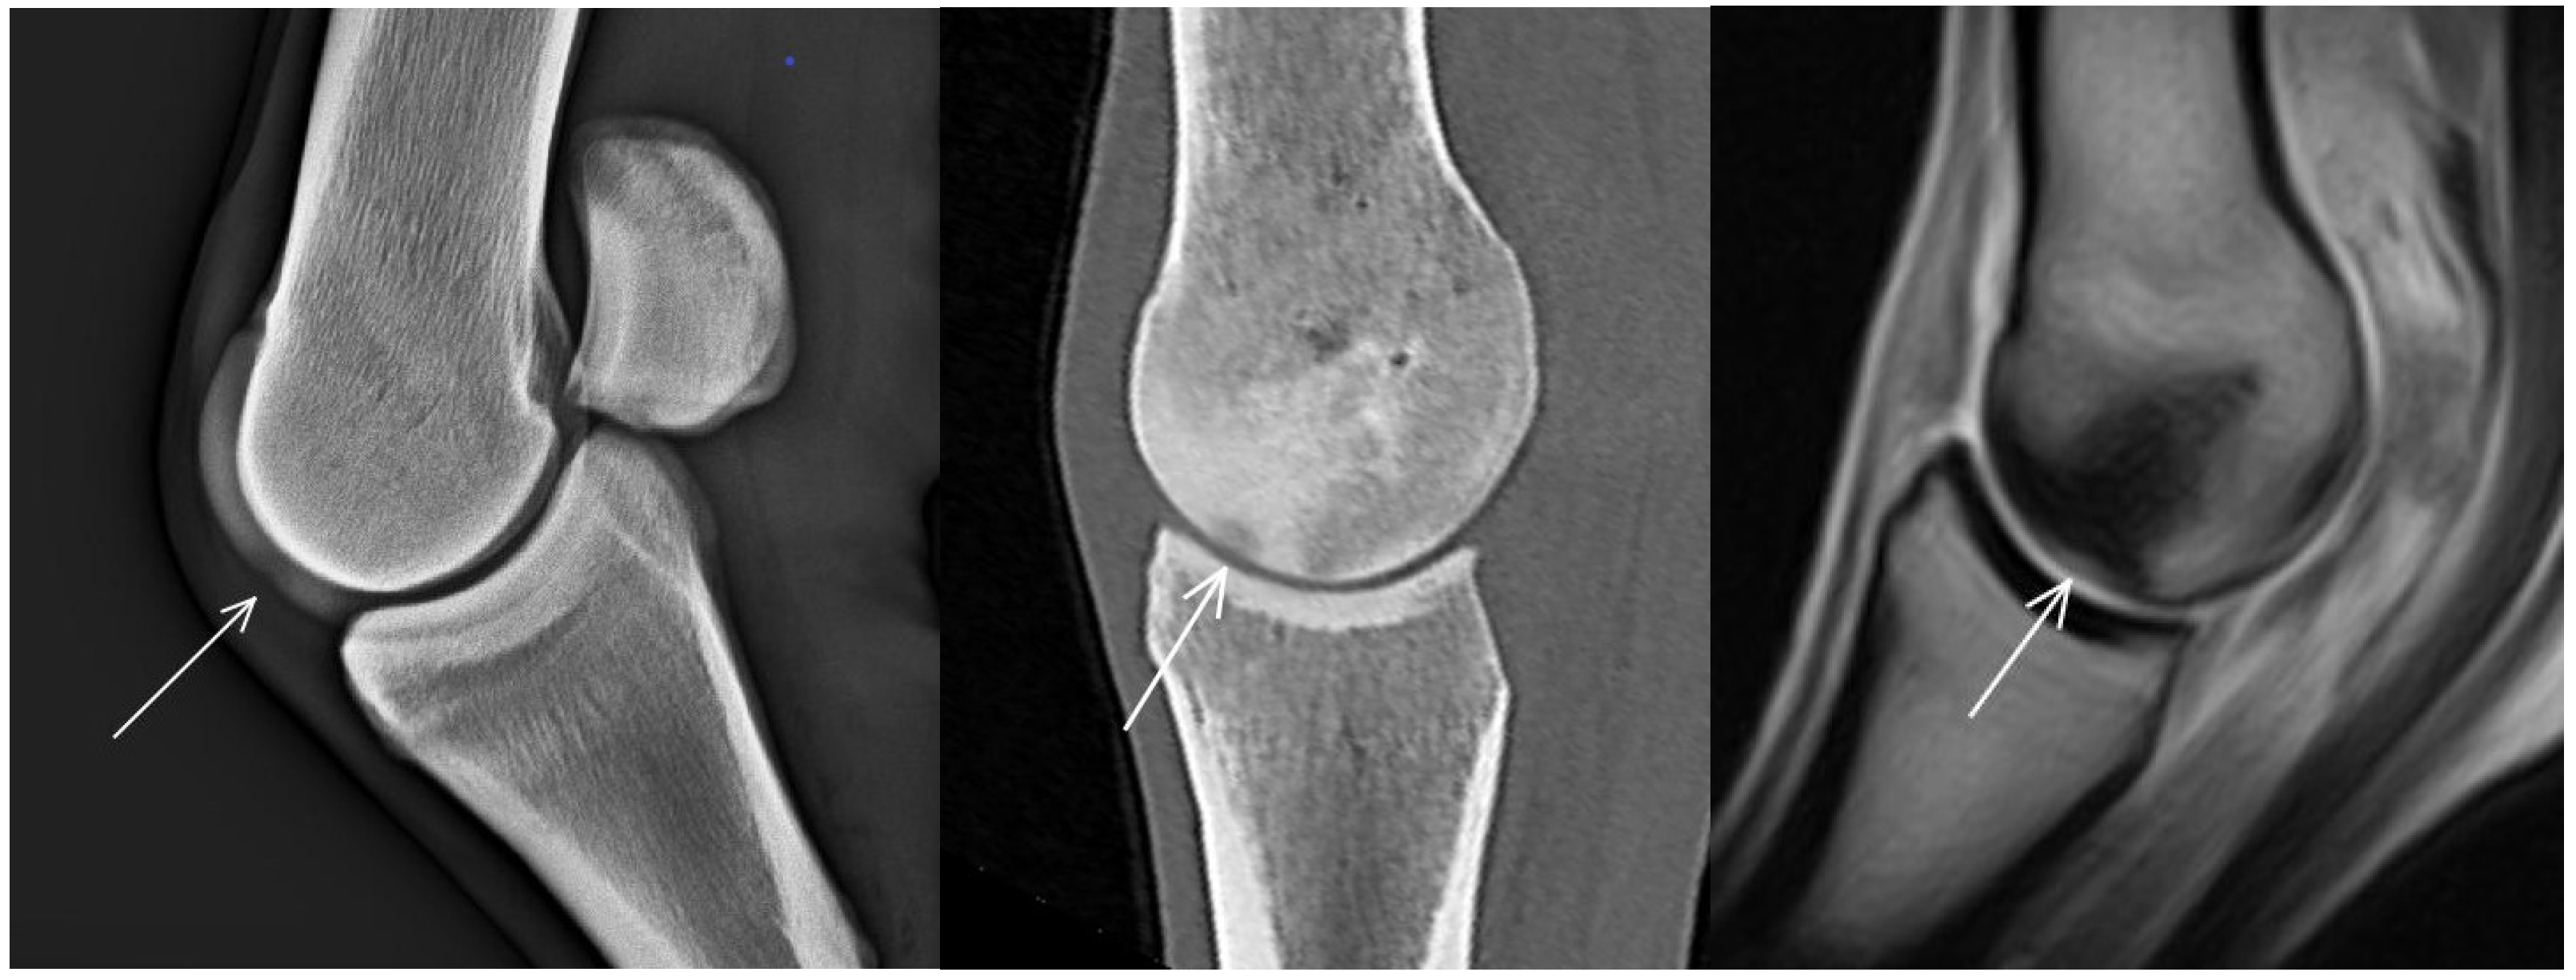

3.1. The Third Metacarpal Bone (McIII)

| McIII Sagittal ridge | |||

| Hypoattenuating lesion in the dorsal subchondral bone Subchondral bone thickening Dorsal/palmar half Increased attenuation in the trabecular bone Dorsal/palmar half Cone shaped/patchy Focal separated hyperattenuation | Hyperintense signal in the dorsal subchondral bone Subchondral bone thickening Dorsal/palmar half Decreased signal intensity in the trabecular bone Dorsal/palmar half Cone shaped/patchy Focal separated intermediate/low signal intensity | Radiolucent lesion Subchondral bone thickening Dorsal Increased trabecular bone opacity | |